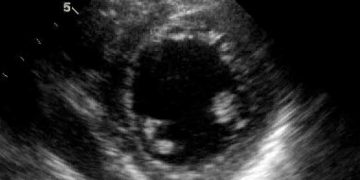

Yalancı Perikarditis, perikardiyum dışında oluşan apse, ekinokok keseleri, tümör, tek taraflı plöritis, tüberkülöz, lökoz gibi hastalıklarda mediyastinal lenf yumruları büyümeleri ...